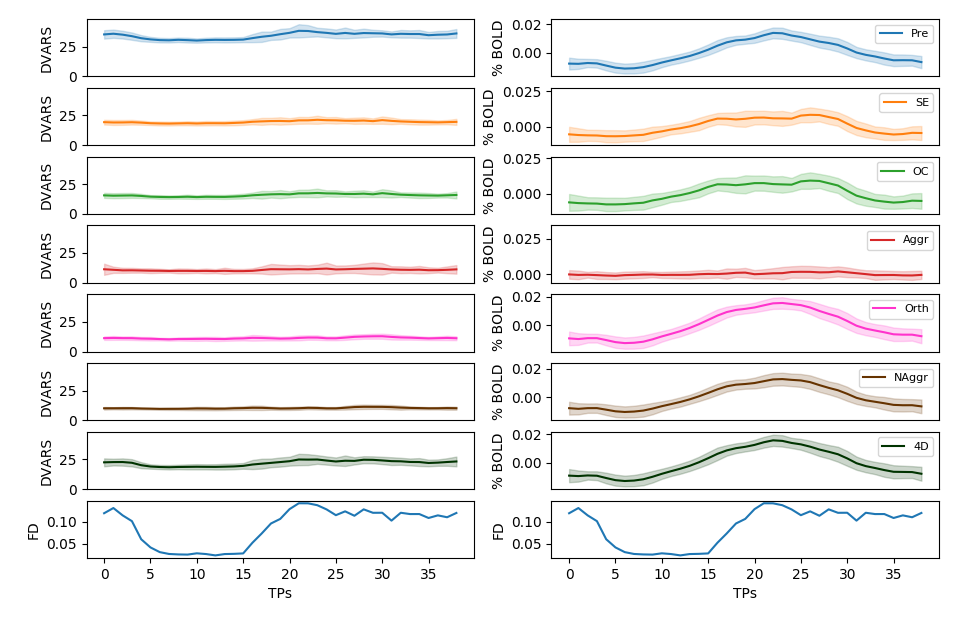

Alternative ICA based denoise (sequential)

Average % BOLD and DVARS across all trials

↑

↑

↓

↓

↓

↓

↓

Aggressive denoise removes signal of interest

OC and E-02 denoise affects the signal of interest more than ICA denoise

↑

↑

↑

↑

Alternative ICA based denoise (sequential)

Results: motion removal

Moia et al. 2021 (NeuroImage)

Results: model comparison

Moia et al. 2021 (NeuroImage)

CVR amplitude

CVR lag

CVR amplitude

CVR lag